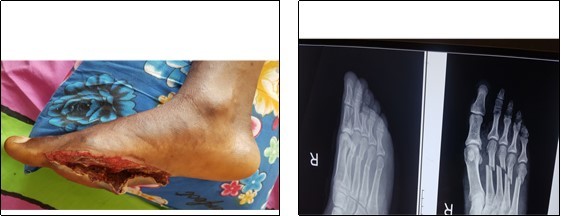

The open foot injuries in this study were treated by initial wound debridement followed by other procedures depending on the nature of the injury. Lacerations were debrided and sutured; where tendons were severed they were repaired as necessary, using standard repair methods. Open fractures were, after debridement, stabilized with K-Wires and thereafter, reinforced with a Plaster-of-Paris slab. Where skin defects could not be sutured, wound coverage was achieved by split skin grafting. None of the 81 patients studied required flap cover for a soft tissue defect. (Figure 1, Figure 2).

Figure 1.Open fracture of the shafts of the right 2nd, 3rd ,4th and 5th metatarsals, treated by normal saline irrigation, debridement and kirchner wire stabilisation.